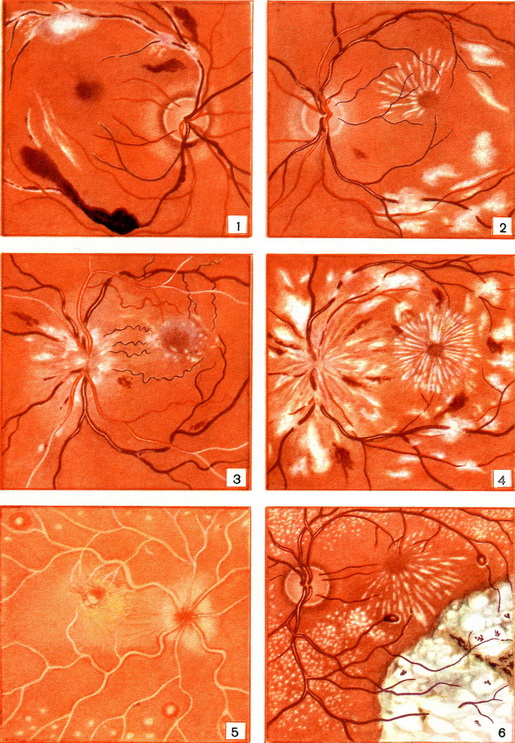

Рис. 1 - 6. Очне дно. Рис. 1. Туберкульозний перифлебит сітчастої оболонки. Рис. 2. Псевдоальбуминурический ретиніт. Рис. 3. Гіпертонічна нейроретинопатия. Рис. 4. Ниркова нейроретинопатия. Рис. 5. Лейкемічна ретинопатія. Рис. 6. Зовнішня ексудативна ретинопатія Коутса.